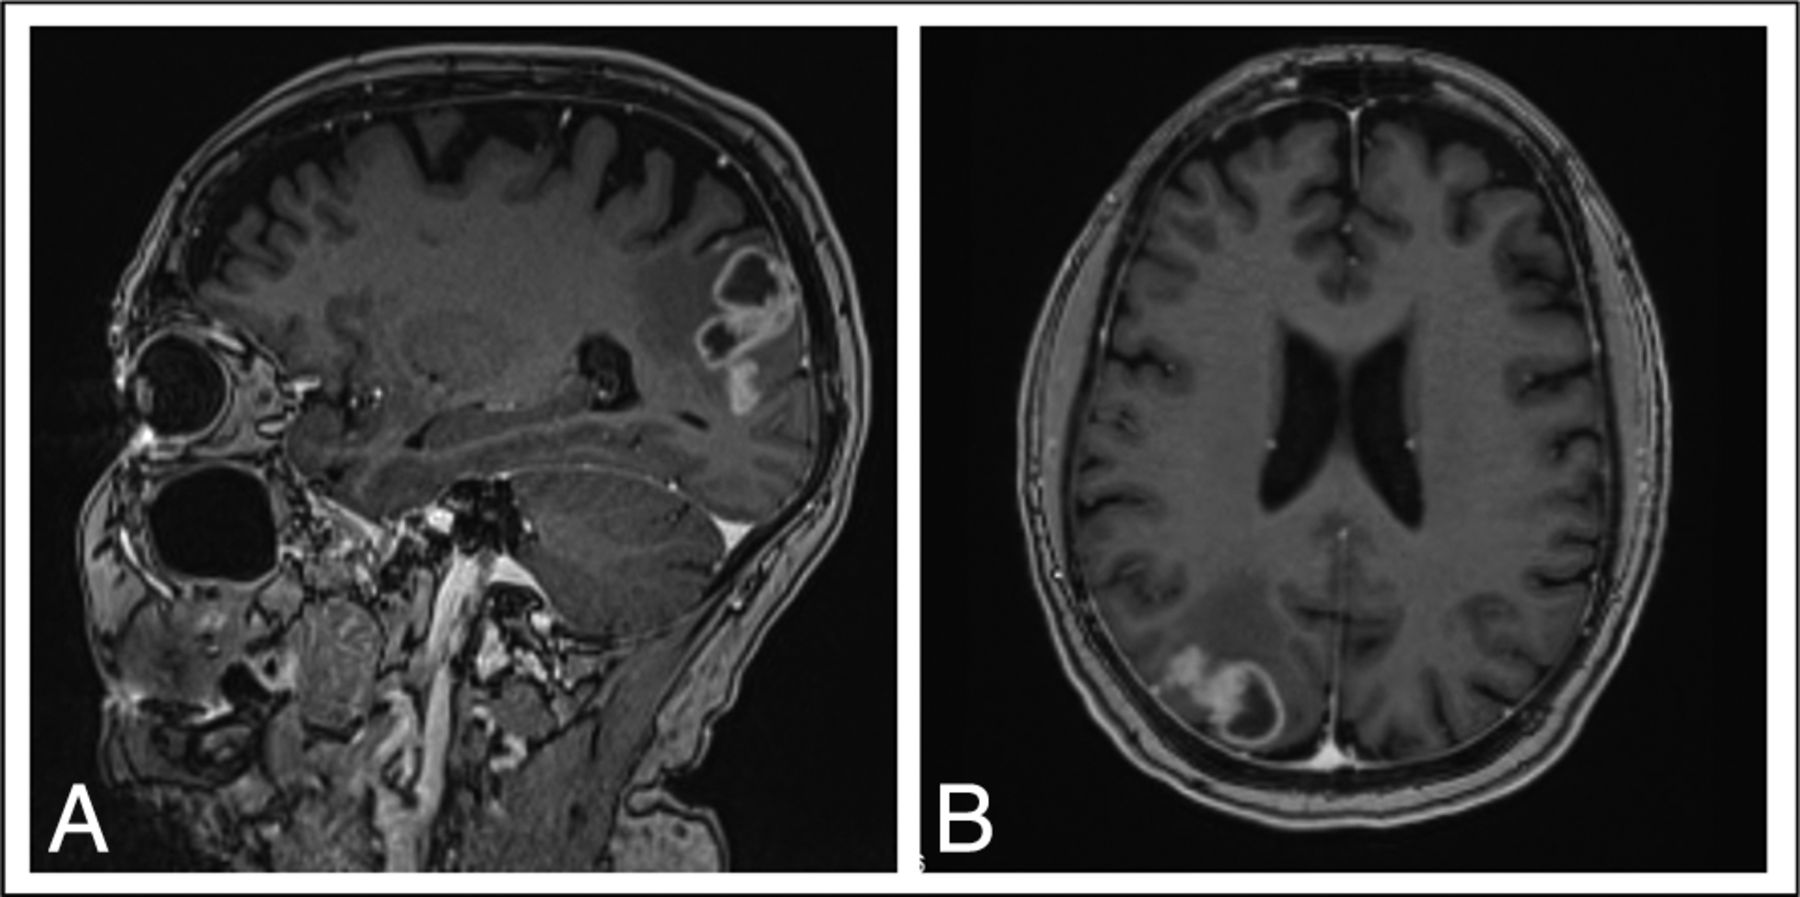

A 49-year-old man with early-stage EGFRm NSCLC (exon 20 mutation) was treated with lobectomy. Eighteen months later he developed right-sided hemiparesis, and a brain MR imaging revealed 3 parenchymal metastases, including one in the left parietal lobe. He was treated with WBRT followed by carboplatin and pemetrexed, and his hemiparesis resolved. Fourteen months later, a lesion in the left parietal lobe progressed consistent with FLIP (Fig 4). The lesion was treated with salvage stereotactic radiosurgery; however, an MR imaging 3 months later showed progression. During that same period, he progressed extracranially and began treatment with pembrolizumab. Unfortunately, follow-up MR imaging 6 months later showed continued progression of the FLIP, though the rest of his brain remained stable. He was given the option of surgery, which he declined, and he died 2 months later.

Brain MR imaging for patient 3, a 49-year-old man with EGFRm NSCLC with an enhancing lesion in the left parietal lobe 14 months following WBRT.